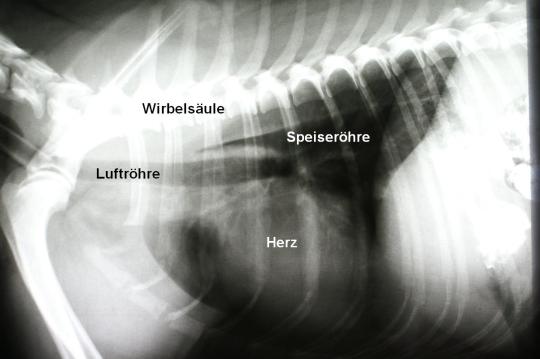

Ein Zusammenhang der Symptomatik mit der Aufnahme des Schweinsöhrchens wird vermutet. In einem ersten Schritt wird deshalb eine Röntgenaufnahme der Bauchregion angefertigt, die aber keine weiteren Aufschlüsse ermöglicht. Deshalb wird dem Hund ein Röntgen-Kontrastmittel verabreicht. Die folgende Röntgenaufnahme zeigt, dass der Magen (wie zu erwarten) mit Kontrastmittel gefüllt ist. Zusätzlich ist aber sichtbar, dass sich auch im unteren Bereich der Speiseröhre noch Kontrastmittel befindet, was nicht normal ist. Eine Röntgenaufnahme der Brust löst dann das Rätsel: In der Speiseröhre befindet sich unmittelbar vor dem Herzen ein grosser, weichteildichter Fremdkörper – offenbar ist ein Teil des Schweinsöhrchens an diesem Engpass steckengeblieben!

Ramira hatte sich beim Fressen des Schweinsöhrchens etwas gar viel zugemutet: Das geschluckte Stück war dermassen gross, dass es in der Speiseröhre des 7 kg schweren Hundes stecken blieb – und zwar in der Region des Herzens, was eine typische Lokalisation darstellt, da hier die Speiseröhre besonders eng ist. Glücklicherweise war der Fremdkörper weich und ohne Kanten und konnte ohne Verletzung der Speiseröhre entfernt werden: Werden scharfe, harte Gegenstände verschluckt und bleiben in der Speiseröhre stecken, kann eine endoskopische Entfernung über die Speiseröhre (d.h. unblutig) praktisch unmöglich oder mit einem hohen Risiko einer Speiseröhrenverletzung verbunden sein. Im Gegensatz zur Bauchhöhle ist eine chirurgische Fremdkörperentfernung aus der Brusthöhle mit viel höheren Risiken, Kosten und Belastungen für den Patienten verbunden.